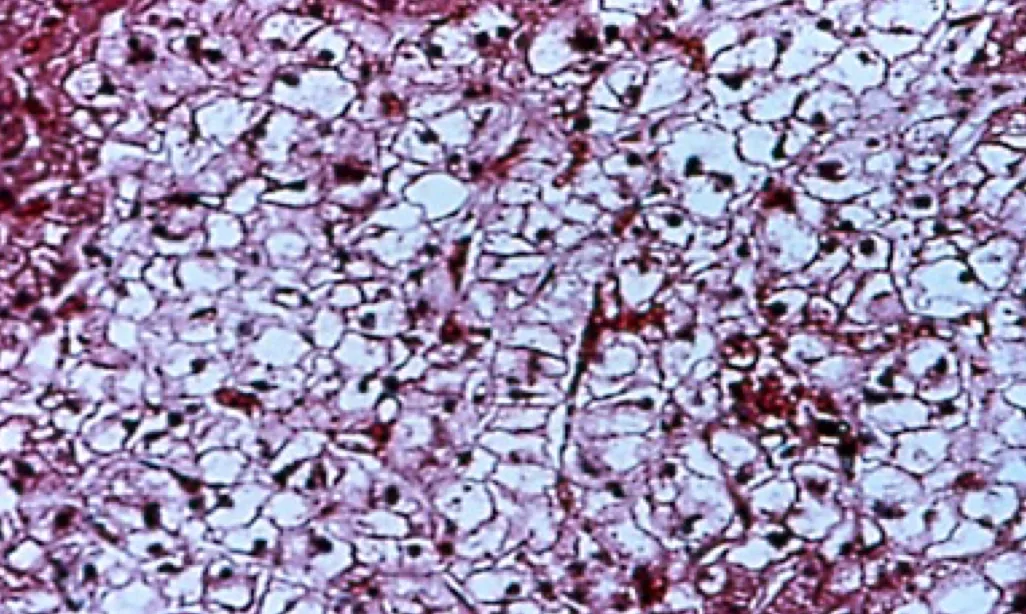

Hepatic biopsy: Identify primary hepatic disease, such as lipidosis, neoplasia, vascular, or inflammatory/fibrotic disease. Steroid hepatopathy is characterized by the presence of vacuoles in hepatocytes, which most studies suggest are filled with glycogen5 (Figure 1). May be associated with endogenous or exogenous administration of corticosteroids or with endogenous excess of other adrenal steroids, such as 17-hydroprogesterone.10

Steroid hepatopathy in a dog on immune-suppressive doses of prednisone